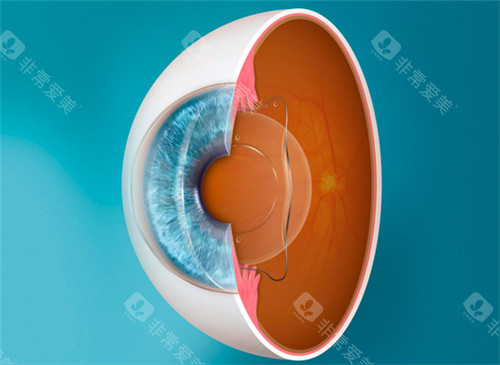

ICL晶体植入手术作为高度近视矫正的主流方案,凭借其可逆性、不损伤角膜的特点,成为越来越多近视患者的选择。

单纯高度近视(≤1800度)

角膜偏薄或干眼症患者

不损伤角膜:适合角膜薄、干眼症等激光手术禁忌人群。

视觉质量高:尤其适合较高高度近视(>1000度)患者。